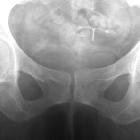

femoroazetabuläres Impingement (Pincertyp)

Pincer morphology refers to an abnormality of the acetabulum or rather an acetabular overcoverage of the femoral head, which may be focal or global, and is one of the causes of femoroacetabular impingement.

AP view of the pelvis and a lateral femoral neck view is recommended for the initial evaluation . Cross-sectional imaging is recommended for the detection of chondral and labral lesions and preoperative planning .

Plain radiograph

Radiographic measures of pincer morphology include the following :

- ilioischial line for assessment of coxa profunda

- increased lateral center-edge angle > 40°

- acetabular index

- crossover sign

- ischial spine sign

- posterior wall sign